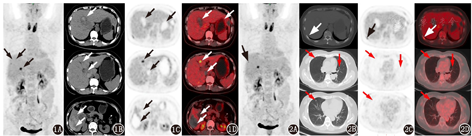

为进一步明确病变性质及全身情况,行18F-脱氧葡萄糖(fluorodeoxyglucose, 18F-FDG;本科室自行制备)PET/CT(德国Siemens Biography 16)显像。结果示:(1)肝多发占位性病变伴出血坏死,最大约7.2 cm×6.7 cm,病变多数呈放射性摄取稀疏,少数呈放射性浓聚,最大标准摄取值(maximum standardized uptake value, SUVmax)为8.5(图1);双肺多发类圆形结节,边界清晰,最大约0.5 cm×0.5 cm,未见明显放射性摄取(图2);右侧第9后肋局部异常放射性摄取(已排除外伤),SUVmax为4.1(图2)。(2)甲状腺放射性摄取弥漫性增高,SUVmax为13.7。PET/CT诊断结果:(1)肝原发恶性肿瘤伴双肺及右侧第9后肋转移可能性大,建议行活组织检查;(2)甲状腺炎。PET/CT检查2个月后,患者复查胸部CT显示双肺结节增大,最大结节为1.1 cm×1.0 cm。

血管球瘤通常发生在真皮中的血管球体或四肢末端的皮下组织,如甲床、手掌、前臂及足部[4]。由于缺少血管球体,血管球瘤很少发生在内脏器官,个案报道包括发生在胃[5,6,7]、肝[8]和肺[9,10]等。本例为罕见的肝原发恶性血管球瘤,CT及病理提示肝内大多数病变有明显出血及瘀血,因此PET图像大多数病变呈放射性摄取稀疏,而肝左外叶一较小病灶无明显出血或瘀血,表现为明显的放射性摄取。患者2个月后复查的胸部CT示:肺内结节明显增大增多,因此肺内结节应为转移灶;右侧第9后肋在形态上无明显异常,是否为转移灶尚需要进一步随访。肝原发血管球瘤的个案报道中,CT平扫病灶呈低密度,增强后边缘清楚,肿块表现为富血供,持续强化,以周围环形强化及中央分隔强化为主[11,12]。因此,肝血管球瘤应作为肝血管肉瘤、肝血管内皮细胞瘤、肝血管外皮细胞瘤、肝不典型血管瘤等病变的鉴别诊断。